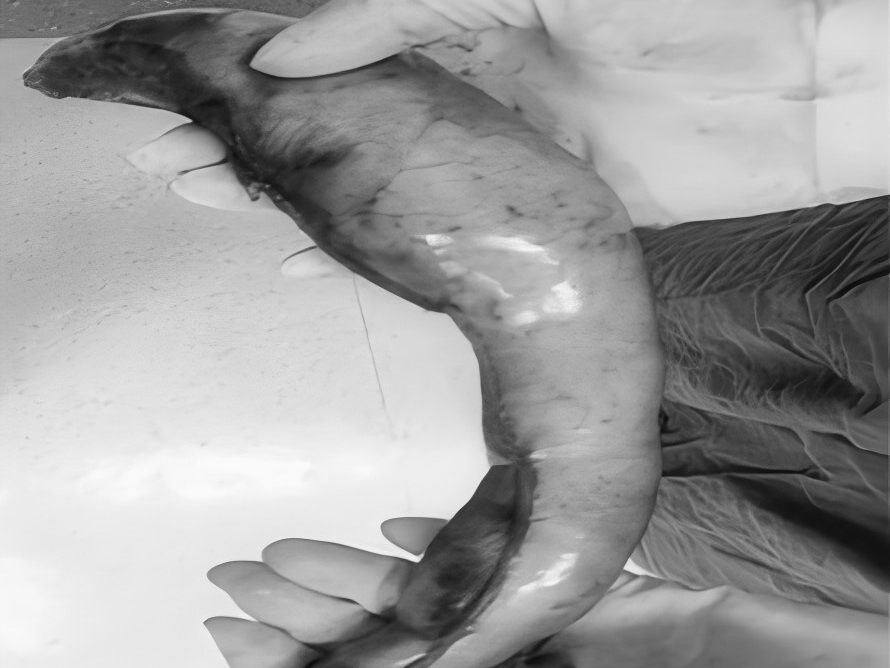

8月27日,贵州航天医院第75次晨读会由我院柔性引进的知名肛肠外科专家高大勇教授作学术交流,他以“肛肠科常见病浅谈”为题,系统讲解了痔疮、肛裂、肛周脓肿等常见肛肠疾病的症状表现、潜在风险及相应治疗方式,为医院带来了前沿医疗理念与技术,有效提升了医务人员对肛肠疾病的早期识别与诊疗水平,也为学科建设、临床诊疗能力的长效提升奠定了坚实基础。 贵州航天医院 普外科专家简介 高大勇 普外科(肛肠外科)学科带头人、名誉主任,主任医师、教授 临床擅长:对中西医结合诊治肛肠学科各种常见病、多发病及疑难杂症等具有丰富的临床经验。 原遵义市第一人民医院(遵义医科大学第三附属医院)、遵义市中医院肛肠科主任。中华中医药学会肛肠分会常委,全国中医肛肠学科名专家,中国健康促进与教育协会肛肠分会常委,中国康复医学会肛肠疾病康复专业委员会常委,中国民间中医医药研究开发协会肛肠分会副秘书长,中国医师协会中西医结合肛肠医师专业委员会常委,国家二级心理咨询师,贵州省第一批中医名医工作指导老师,遵义市名中医,遵义市肛肠学会会长,遵义市肛肠质控中心名誉主任,遵义市中西医结合学会名誉会长,遵义市健康科普专家,原贵州省中西医结合学会肛肠分会副主任委员、贵州省中医肛肠质控中心副主任、遵义市医学会医疗鉴定委员会专家、遵义市卫生系列高评委。发表论文30余篇,主编和参编医学著作5本,主持省级科研课题2项、市级科研课题2项、院级科研课题1项。 梁   跃 中共党员,普外科党支部书记、主任,主任医师 临床擅长:对普外科各类肿瘤手术具有丰富的临床经验。 毕业于遵义医学院,遵义市医学会小儿外科学分会常务委员,遵义市肛肠协会理事,遵义市医学会核医学分会(第二届)委员会委员;荣获第三期“黔医人才计划”优秀学员称号;主持市级课题1项,完成省级课题1项,在国内各类刊物上发表论文10余篇。 钱科洪 民盟盟员,普外科副主任医师 临床擅长:从事普外科临床工作30余年,对各类普外科疾病的诊治、乳腺、甲状腺、胃十二指肠、结直肠等疾病及疑难杂症具有丰富的临床经验。 毕业于遵义医学院临床医疗系,2009年前往中山大学附属第一医院微创外科进修学习,在国内各专业期刊发表论文数篇。 贵州航天医院 普外科简介 基本情况 贵州航天医院普外科成立于1968年,前身属于航天部O61基地3417医院外一科,1998年3417医院、3427医院合并后更名为普外科,下设胃肠外科、肛肠外科2个亚专业科室,拥有在全市较为先进的专科设备和技术,是中国疝病专科联盟单位,贵州医科大学附属医院胃肠外科专科联盟单位。开放床位40张,配备医护人员21人。 专科特色技术 普外科致力于胃肠及肛肠疾病的外科临床诊治及科研,以腹腔镜微创外科技术为本,形成以快速康复治疗胃肿瘤、结直肠肿瘤、小肠肿瘤、直肠脱垂、肥胖病、急腹症、各类疝、痔、瘘等专科特色,同时注重胃肠疾病尤其是结直肠恶性肿瘤的基础研究和临床转化研究,总体诊断和治疗水平在区域同级医院居于领先水平。 开展手术:腹腔镜下胃癌根治术,腹腔镜下袖状胃切除术,腹腔镜下胃肠道间质瘤切除术,腹腔镜下结、直肠癌根治术,胃癌、结直肠癌的精准治疗,腹腔镜下小儿疝气、成人疝修补术,腹腔镜下阑尾手术,内痔的硬化注射治疗及痔疮的微创治疗:ATH、PPH、TST,直肠脱垂的各种手术治疗,难治性伤口VSD技术,鼻胃肠管、肠梗阻导管置入术,肛肠术后间歇性导尿技术,并引进了中医适宜技术,也为各种化疗患者提供输液港安装,提高患者就医体验。 腹腔镜下腹股沟疝 无张力修补术 腹股沟疝里金斯坦(Lichtenstein)手术 PPH微创术治疗环状混合痔 黏连性或炎性肠梗阻-肠梗阻导管 腹腔镜袖状胃切除 腹腔镜阑尾切除术 腹腔镜阑尾肿瘤切除术 腹腔镜下结肠癌根治术 科室诊疗范围 胃肿瘤、结直肠肿瘤、小肠肿瘤、肥胖症、各类急腹症、腹部外伤、腹壁疝、便秘、直肠脱垂、痔疮、肛瘘、肛裂等胃肠、肛肠外科疾病。 end